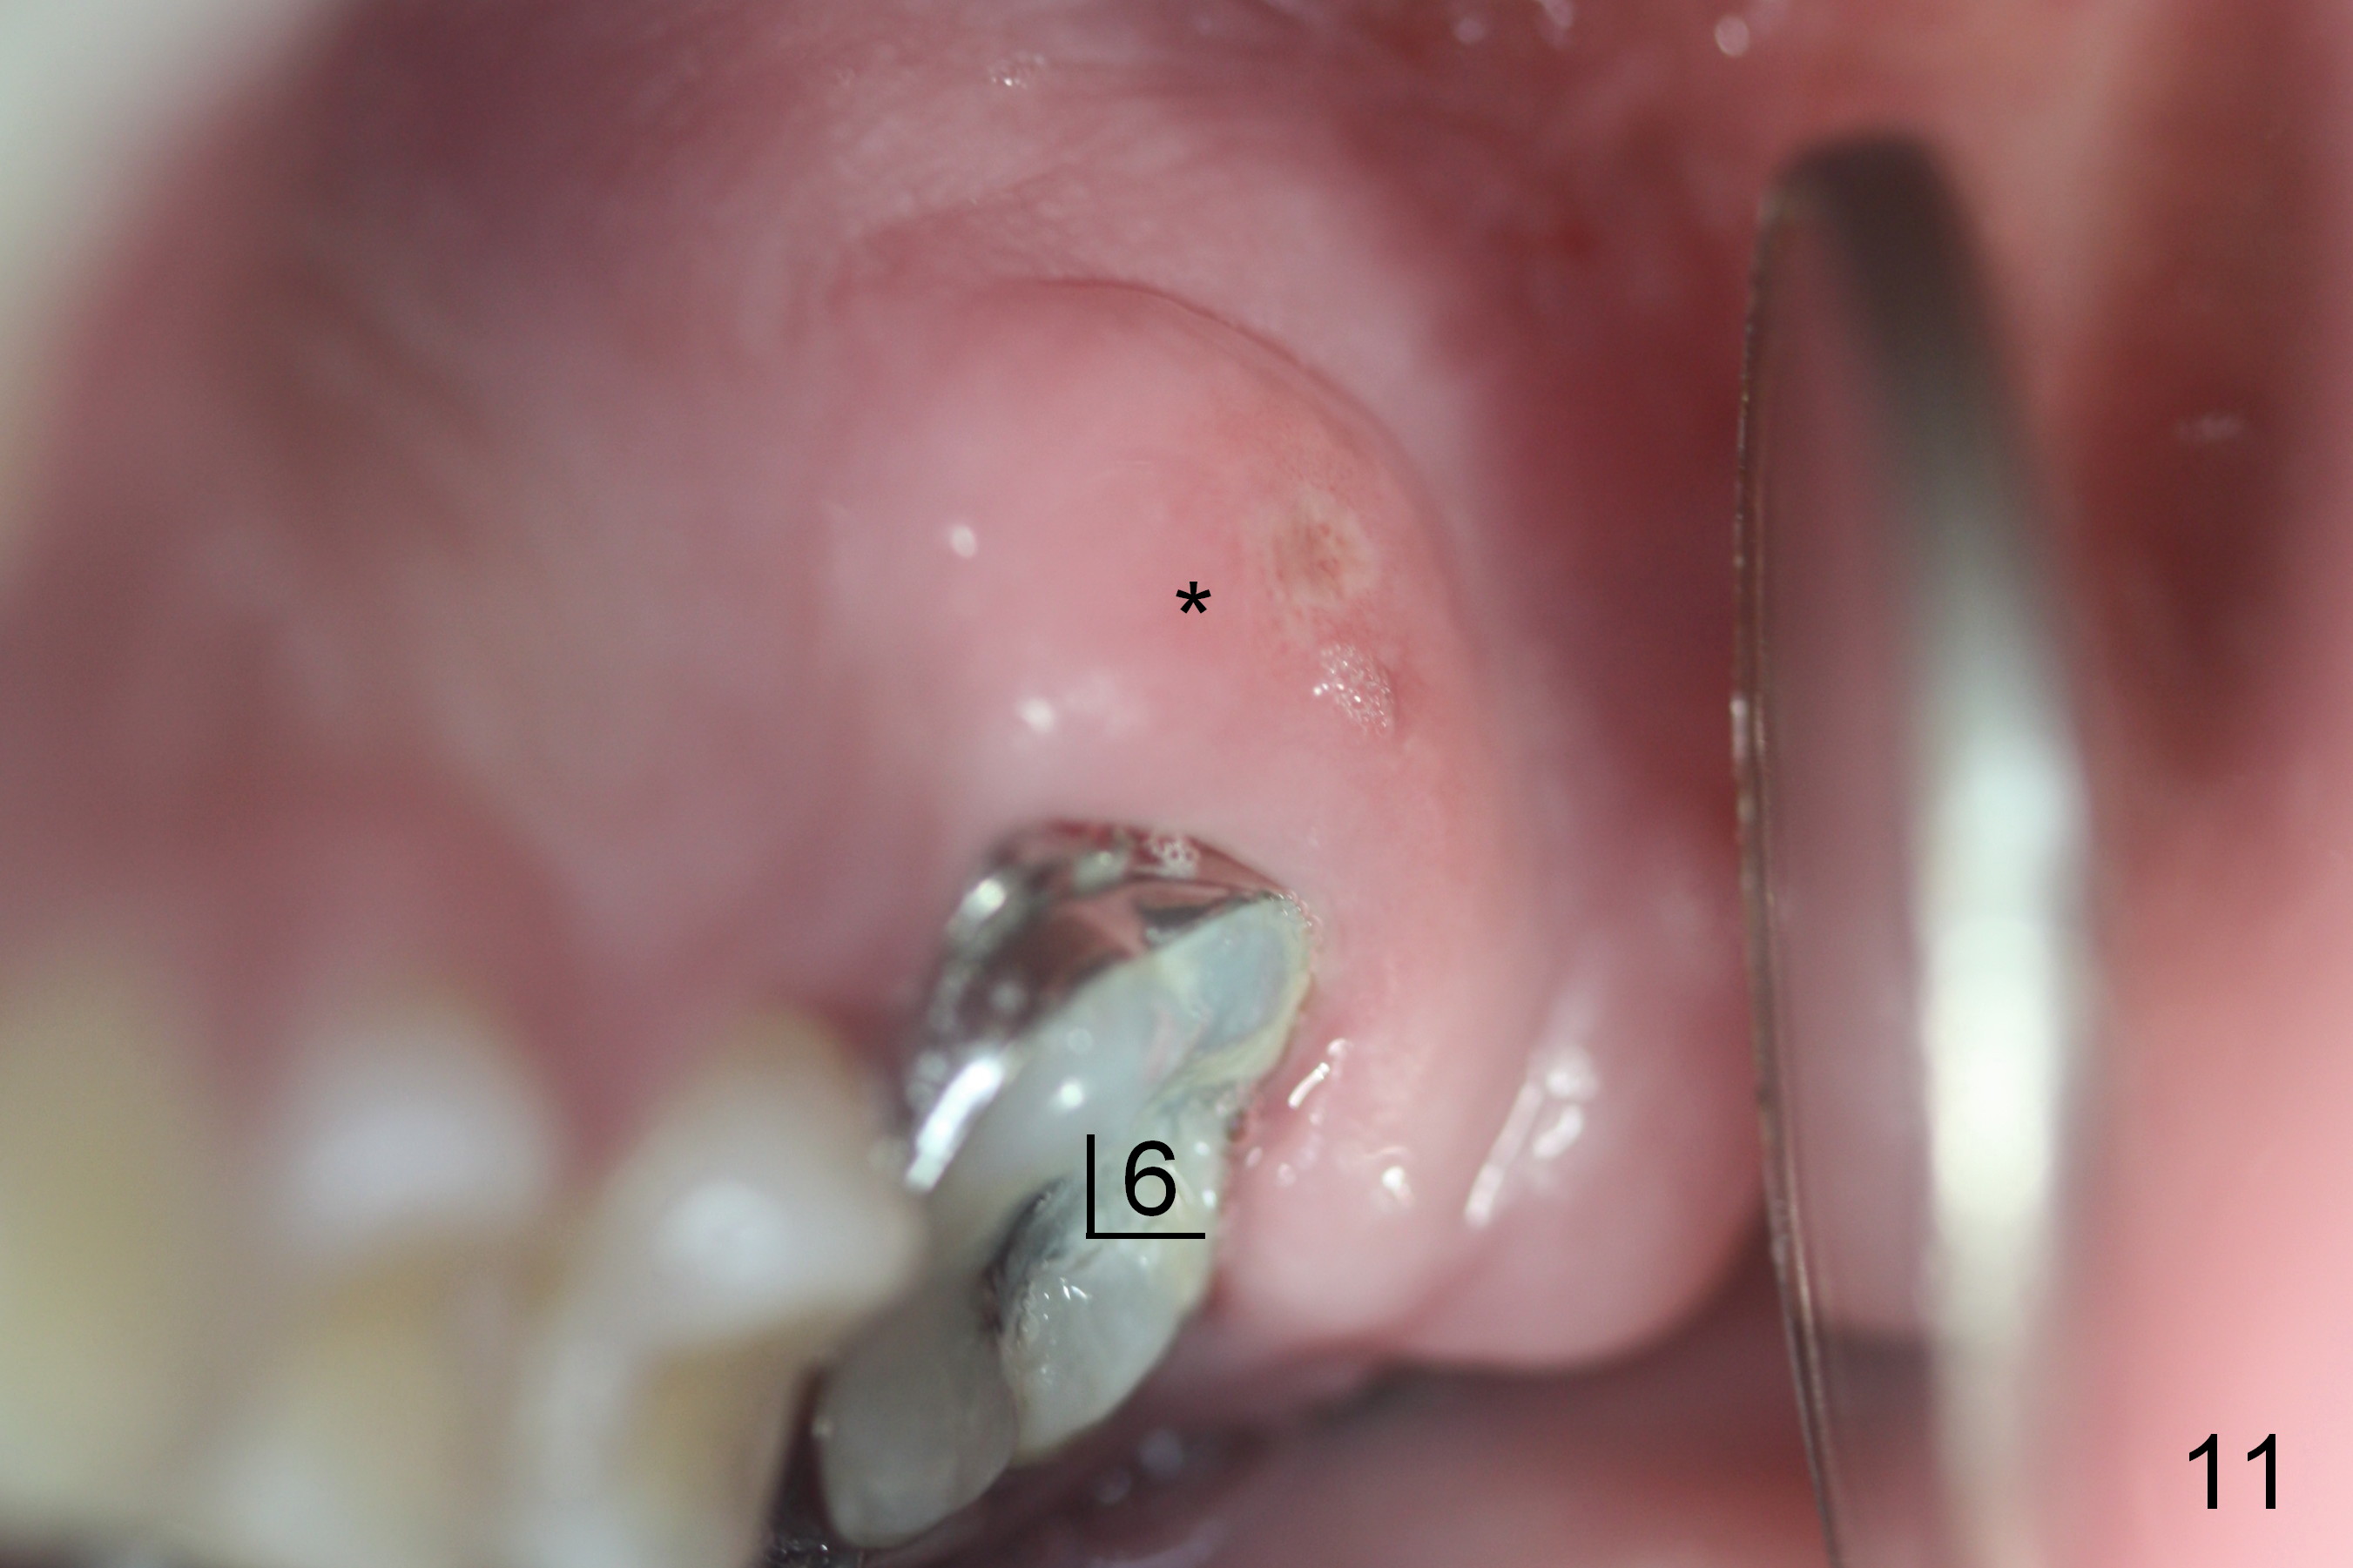

On March 9, 2016 (11.5 months of treatment), periodontal abscess develops around UR6 (Fig.11 (palatal view) *). It appears that the molar band as well as the buccal tube (Fig.12 *) is embedded into the gingiva. One week after band removal (as well as posted wire and closed coil springs), the infection resolves (Fig.14). As compared to preop Panoramus (Fig.13), the upper arch distalization is mainly at the crown level (Fig.4 arrows). The miniimplants should be placed higher (at the zygomatic arch); the post should be taller. Therefore the roots can be distalized as well (click the link below).